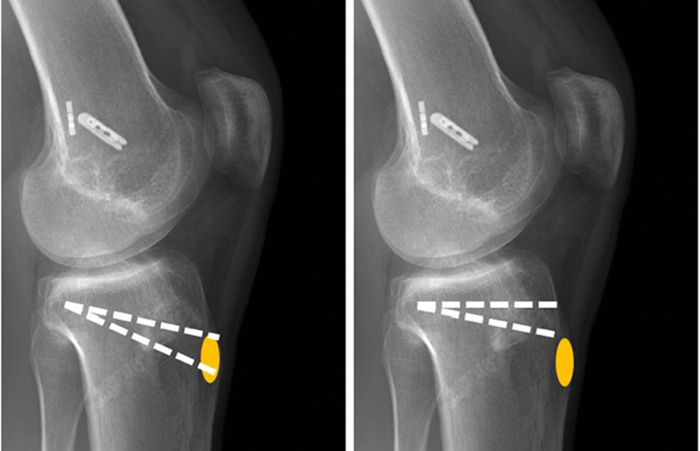

Osteotomi ameliyatı

DOME Shaped

Osteotomi ameliyatı

Close wedge

Bu operasyonda, bacaktaki dizin sağlıklı kısmının altından veya uyluğun alt kısmından üçgen veya kama şeklinde bir kemik çıkarılır ve boşluk kapatıldıktan sonra, uzvun uzantısı düzeltilerek bir cihazla sabitlenir. (Çıkarılan kemik miktarı deformitenin büyüklüğüne bağlıdır ve farklı şekilde modifiye edilmesi gerekir). Bu yöntemde vücut biraz daha kısalır.

Osteotomi ameliyatı

Açık kama

Açık kama osteotomi ameliyatı, belirli kemik sorunlarını tedavi etmek için kullanılan cerrahi bir işlemdir. Bu yöntemde, cerrah kemiğe erişmek için kemikte gerekli alanı açar. Ardından kemiğin bir kısmını çıkarır ve istenen değişiklikleri yapar.